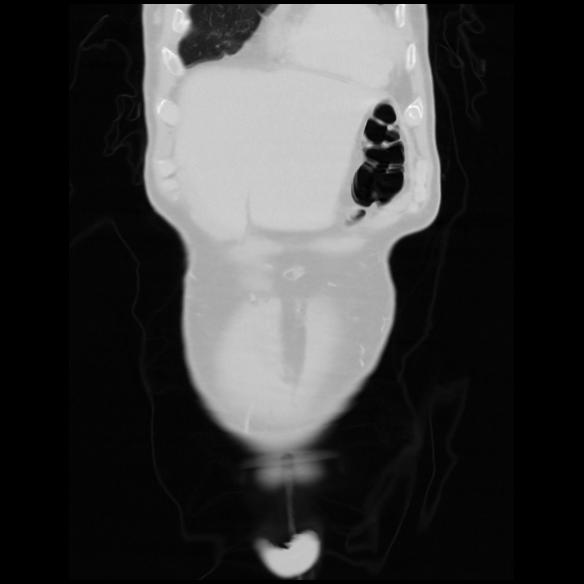

6 CUERPO,CE,Coronal,3.000,CUERPO,Coronal,